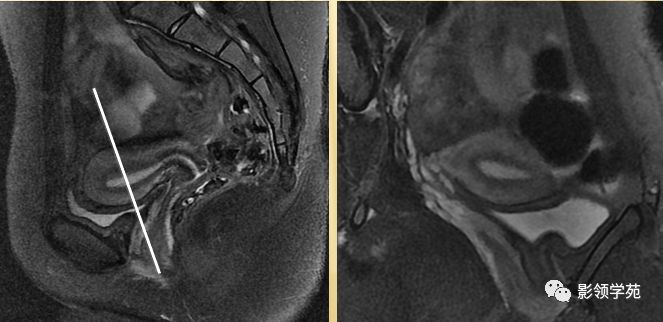

- 呈前倾前屈位

- 屈:宫体与宫颈间夹角为170度

- 倾:宫体与阴道间夹角为90度

T2WI : 宫体三层:

中心高信号---子宫内膜和分泌物;

中间低信号带---子宫肌内层,亦称结合带;

周围呈中等信号---子宫肌外层

T2WI图像可显示子宫体三层

结构

- 子宫内膜-高信号

- 结合带-低信号

- 子宫肌层-中等信号

子宫体正常MRI表现

T2WI :

宫颈四层:

高信号---宫颈管黏液

稍高信号---宫颈黏膜皱襞;

低信号---宫颈纤维基质(与宫体JZ连续)

等信号---宫颈肌层